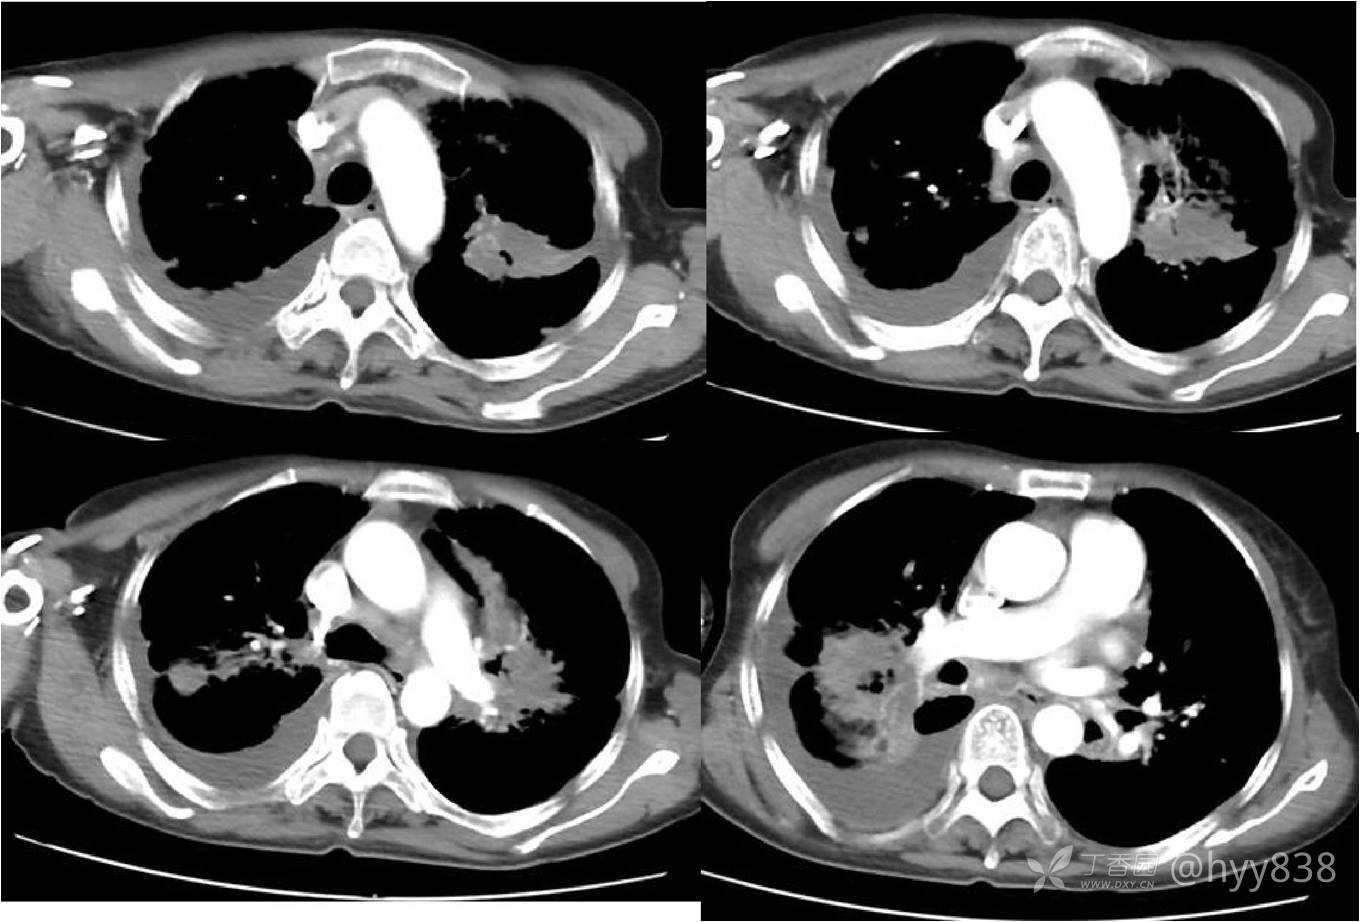

次年行CT复查,病灶进展

增强